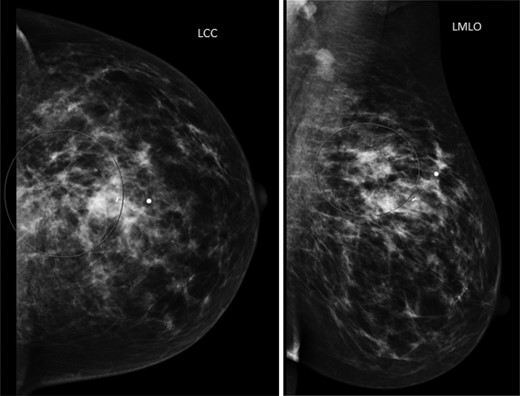

The patient is a 47-year-old Polish premenopausal female who presented with complaints of a non-tender palpable left breast mass for 4 months at an outside institution. She underwent a diagnostic mammogram and ultrasound that reported a 2-cm irregular, hypoechoic mass at 12 o'clock. The mass had indistinct borders on ultrasound (Figs. 1,2). Bilateral breast MRI revealed no disease in either axilla or the right breast. There was a 2.2-cm enhancing mass in the left breast at 12:00 that was consistent with the patient's biopsy-proven malignancy (Fig. 3). Upon examination in the Breast Surgery clinic, she underwent a core needle biopsy, which revealed a poorly differentiated triple-negative invasive ductal carcinoma (Fig. 4).

Left mammogram. The circled area revealed a 2-cm irregular mass with biopsy clip noted.